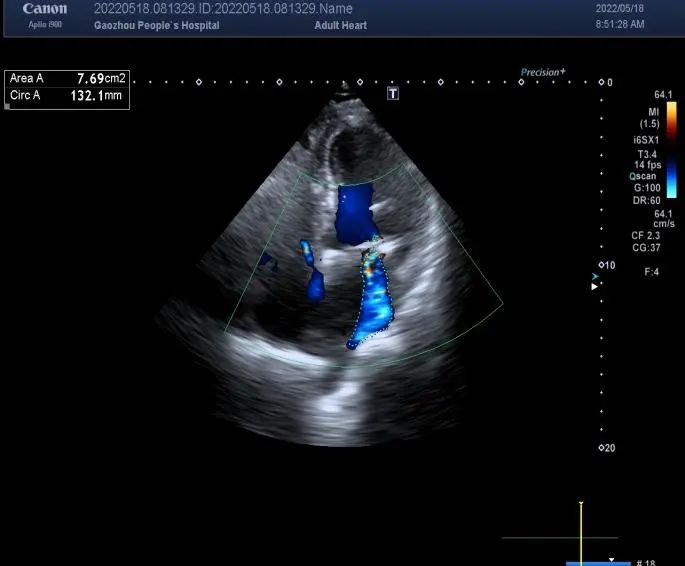

日前,高州市人民医院心血管外科曹勇教授团队为一名71岁换瓣术后27年机械瓣膜功能障碍的女性患者成功实施了双瓣膜瓣环扩大重建+瓣膜替换手术,该手术又称为Commando手术或UFO手术。该患者27年前在高州市人民医院心外科行主动脉瓣机械瓣置换手术,术中使用国产G-K瓣。术后康复出院,长期服用华法林抗凝治疗。1个月前出现气促、腹胀、下肢肿胀,复查心脏彩超提示主动脉瓣流速增高3.3m/s,压差43.56mmHg,二尖瓣、三尖瓣中重度关闭不全,合并严重心衰,有手术的指征,为进一步手术治疗入住高州市人民医院心血管外科一区(见术前心脏彩超图)。